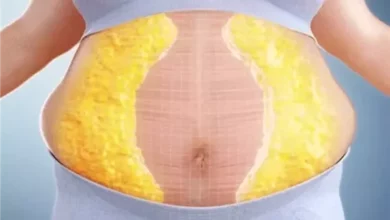

كمية الدهون تحت الجلد حول منطقة السرة.

درجة ارتخاء جلد البطن وعضلاته.